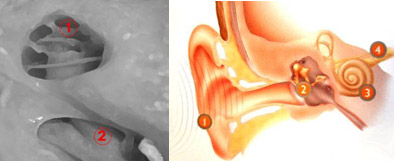

La vía auditiva tiene su primer nivel o neurona, a nivel de la cóclea. Es aquí donde las terminaciones del nervio auditivo se enrollan dos vueltas y media en el caracol formando el Ganglio Espiral. Estas fibras del nervio auditivo se contactan con las células ciliadas de la cóclea que son las encargadas de transformar el estímulo sonoro en un impulso eléctrico. Tenemos ya dos estructuras que son de gran importancia para comprender el funcionamiento de los implantes de tronco: la cóclea y el nervio auditivo.

En la primer imagen observamos la cóclea (1) y el nervio auditivo (2) ingresando para contactar con la células ciliadas de la cóclea. En la segunda imagen un esquema general del oído con la cóclea (3) y el nervio auditivo (4).